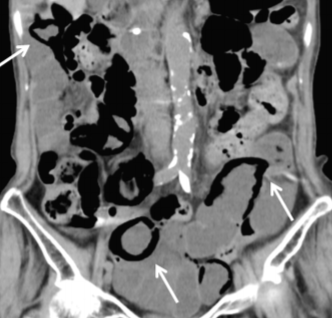

症例4 遠隔画像診断事業 症例紹介 特発性腸管嚢腫様気腫症 株式会社ワイズ リーディング